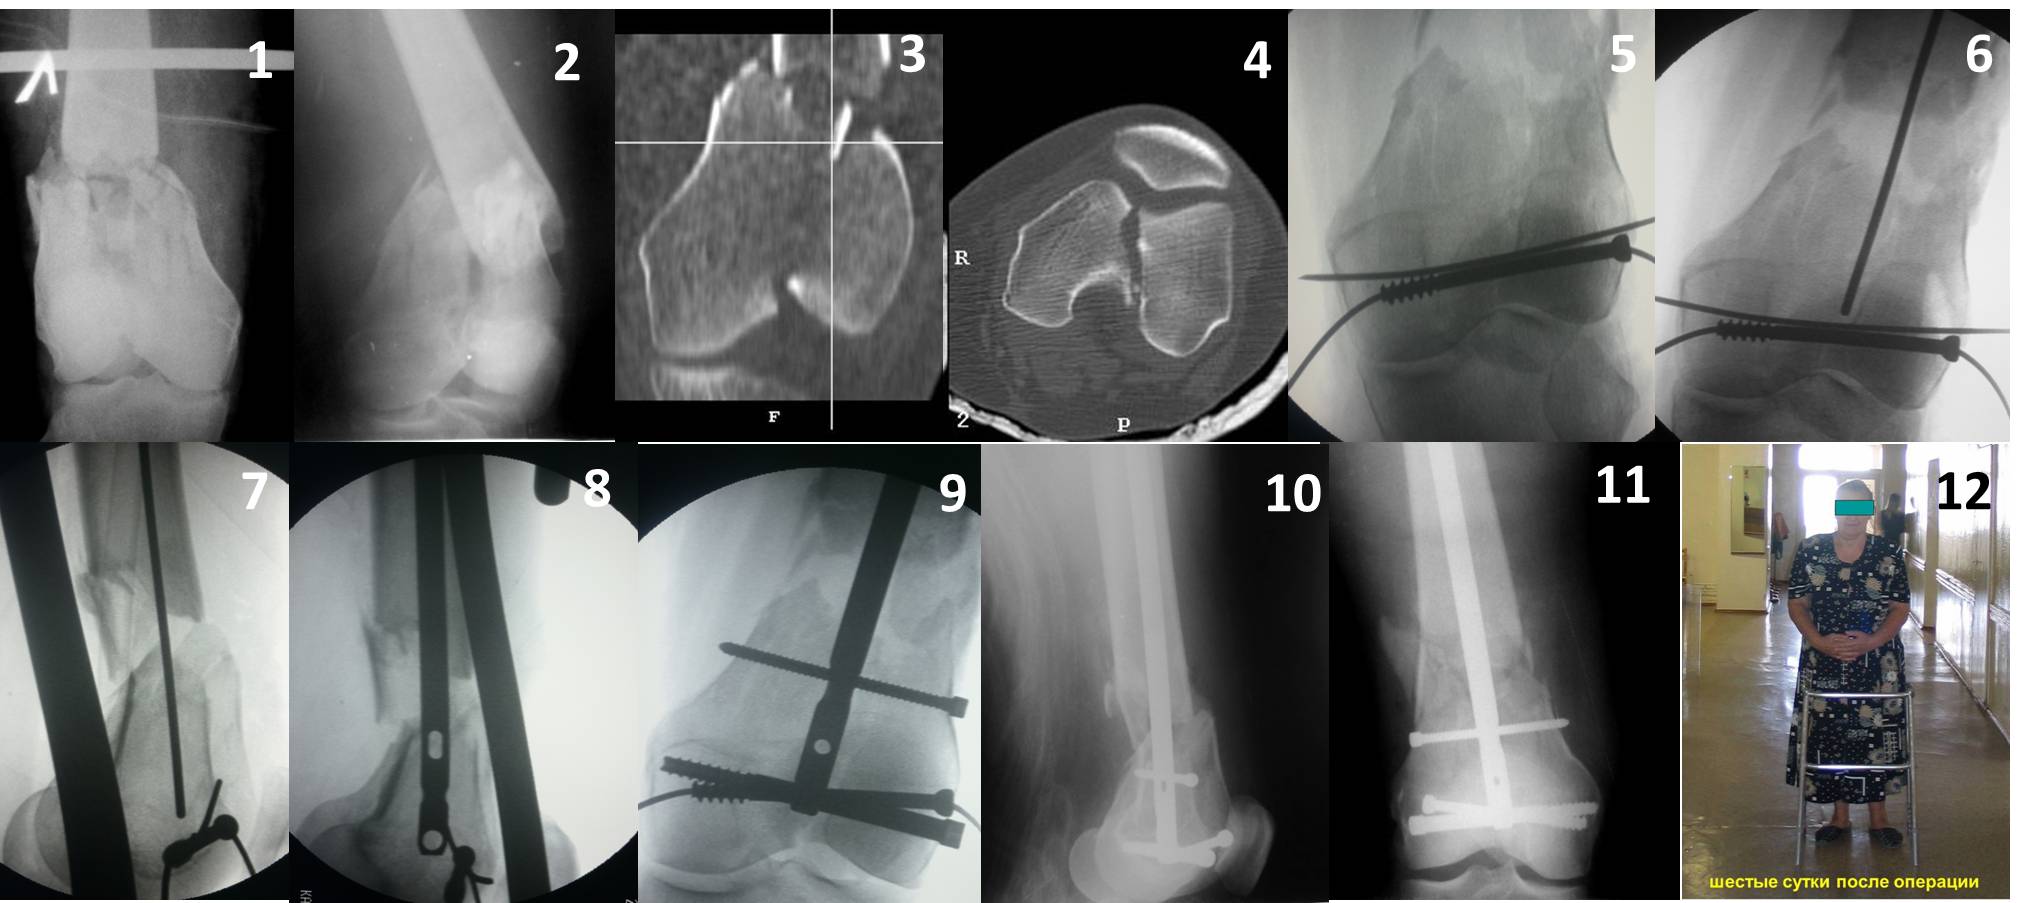

Здесь пример медиальной пластины и латеральный комбинированный метод (у второго больного старый перелом тибиал плато, леченный где то и когда то)

Ответ на эту часть Вашего поста – вложенный файл. Больная оперирована неделю назад по поводу открытого перелома дистального эпиметафиза бедренной кости. После операции она идёт в рентгенкабинет для выполнения послеоперационной контрольной рентгенографии, представленной на слайдах 10 и 11. Узнав, почему её фотографируют, просила передать Вам, Антон, привет.

В приложении пример недавней операции, C3, открытая репозиция, фиксация мыщелков спицами и винтами, ретроградный синтез большеберцовым гвоздем 10,5 мм диаметром, винты 5 мм.